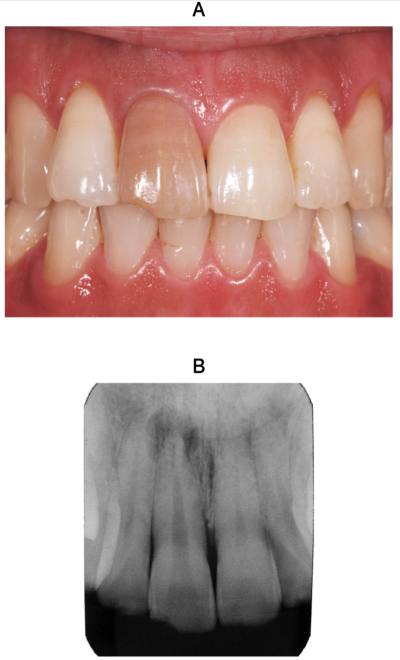

28歳の男性。上顎右側中切歯の審美不良を主訴として来院した。5年前に転倒して1⏌を強打し切縁部を破折したがそのままにしていたという。1⏌に動揺はなく、咬合状態は良好である。歯冠破折部のコンポジットレジン修復と漂白処置を行うこととした。初診時の口腔内写真とエックス線写真を別に示す。